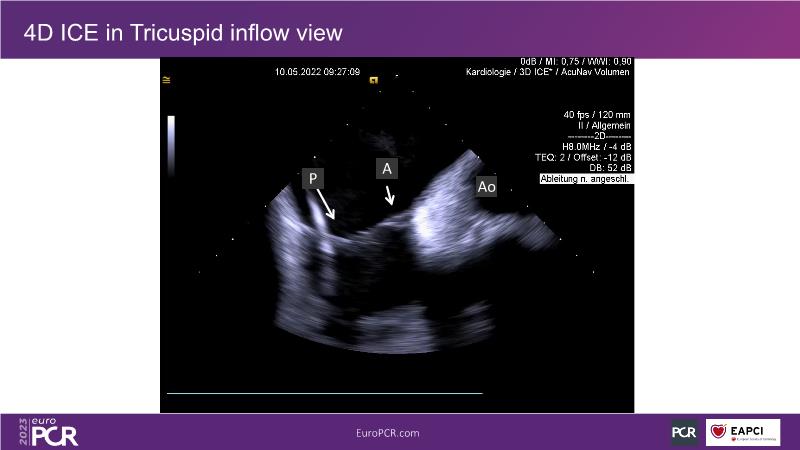

Use of 4D ICE in tricuspid and mitral valve interventions

Watch this session to know the challenges of TV imaging, to get an overview on 4D ICE technology, and to study both a transcatheter tricuspid valve procedure and a transcatheter mitral valve procedure through different case presentations, that will then be discussed.

- To get familiar with the 4D ICE technology and how it can support the imaging and guidance in complex structural heart disease interventions

- To understand the use of 4D ICE and benefits in tricuspid and mitral valve interventions